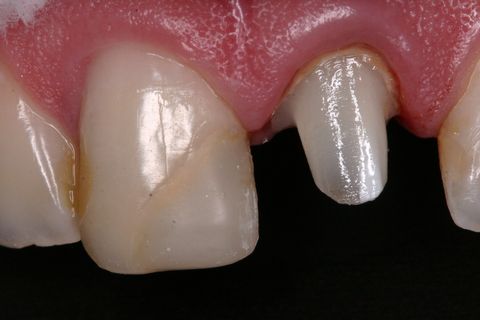

Aspecto Clínico Inicial

Aspecto clínico inicial (vista oclusal)

Paciente jovem do gênero masculino, apresentou-se à Clínica Integrada do Curso de Odontologia da Universidade Severino Sombra necessitando de um tratamento restaurador no dente 21. Ao exame clínico e radiográfico foi observado uma grande destruição coronária e tratamento endodontico satisfatório (Figuras 1, 2 e 3).